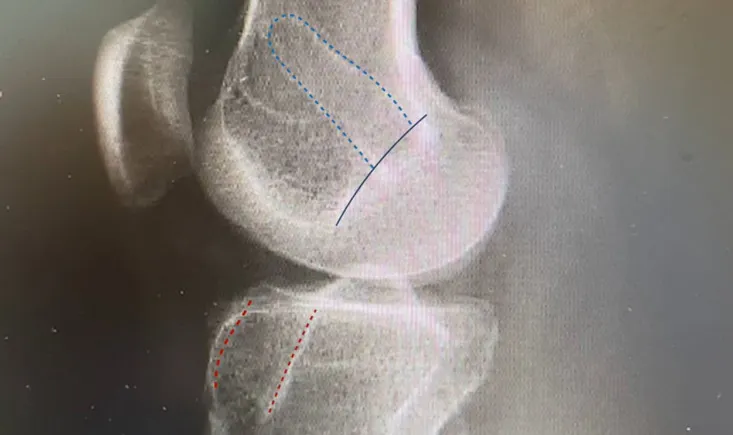

The objectives of this clinical case are to discuss the normal anatomy of the patellofemoral joint and the dif…